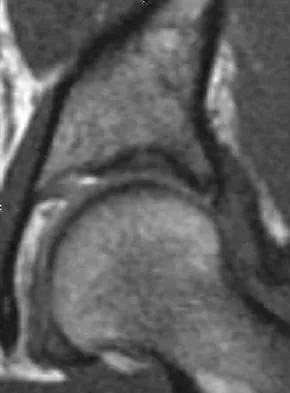

A 19-year-old girl has had pain and swelling in the right ankle for the past 4 months. She denies any history of trauma. Examination reveals a small soft-tissue mass over the anterior aspect of the ankle and slight pain with range of motion of the ankle joint. The examination is otherwise unremarkable. A radiograph and MRI scan are shown in Figures 45a and 45b, and biopsy specimens are shown in Figures 45c and 45d. What is the most likely diagnosis?

Explanation